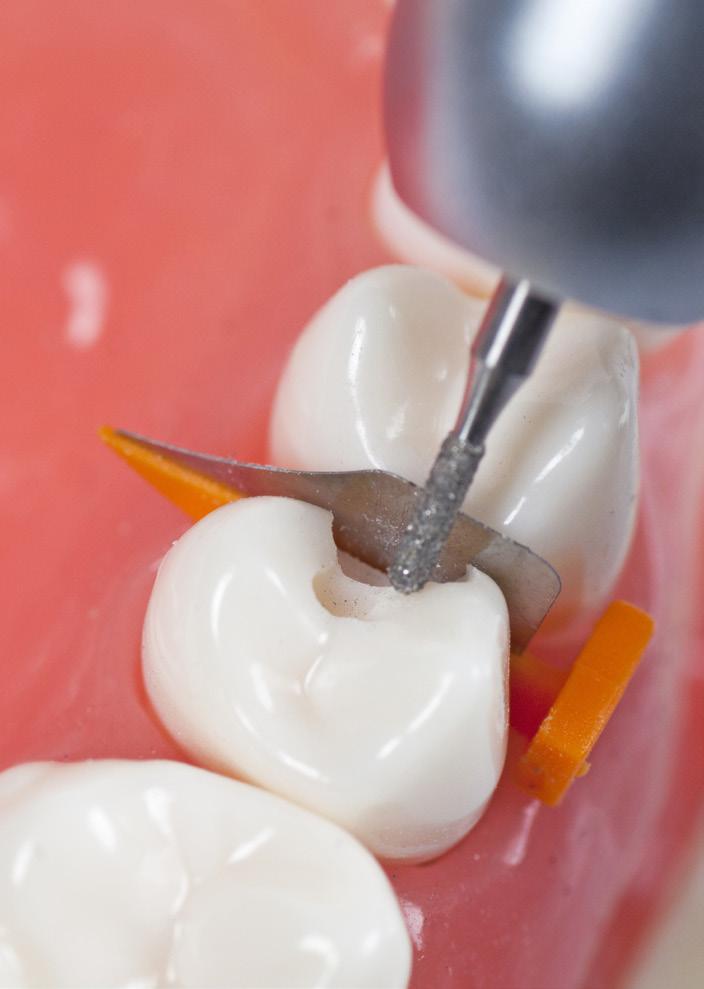

Directa ContacEZ IPR er et sett instrumenter laget for å gjøre interproximal reduksjon, IPR, trygt, raskt og enkelt. Fleksible strips i høykvalitet rustfritt stål, ferdig montert på ergonomisk holder du kan bruke med én hånd. Følger tennenes naturlige konturer, samtidig som de har styrke nok til å lett komme igjennom trange kontaktpunkter. Kan autoklaveres.